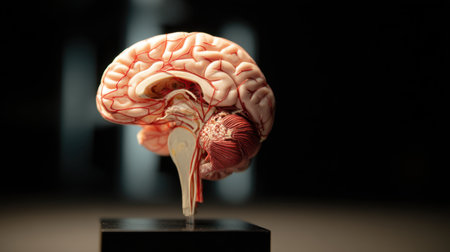

This image features a detailed human brain model, showcasing the vascular structure, set in a modern laboratory environment, ideal for educational materials.

This high-quality image features an anatomically accurate brain model, showcasing intricate vascular structures and the spinal cord, ideal for educational use.